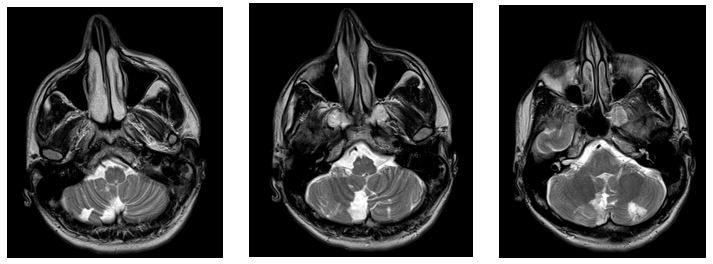

Se realiza una tomografía simple que reporta lesión hipodensa en el lóbulo cerebeloso derecho de aproximadamente 3x3.4 mm, con pérdida del patrón de las folias (sugiere atrofia de tejido); Se valora resonancia magnética contrastada donde se observa en secuencia T2, FLAIR y difusión,  lesión hiperintensa en porción inferior de hemisferio cerebeloso derecho, zona del flóculo así como zona posterior y lateral ipsilateral de bulbo raquídeo, concordante con lesión isquémica en el territorio de la arteria cerebelosa posteroinferior (PICA).

Imagen 1. Resonancia magnética, secuencia FLAIR, lesión hipointensa cerebelar derecha.

Imagen 2. Resonancia magnética, secuencia T2, lesión hiperintensa difusa cerebelar derecha.

Imagen 3. Resonancia magnética, secuencia Difusión, lesión hiperintensa heterogenea cerebelar derecha.